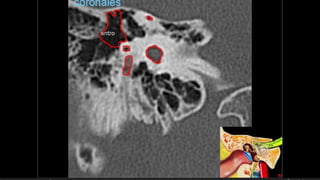

Evaluación Imagenologica

Colesteatoma

 Años después

 Epitimpano, antrum

Colesteatoma  Años después Epitimpano, antrum Teorías  Atrapamiento epitelial en la línea de fractura  Implantación traumática de MT hacia oído medio  Captación de epitelio del CAE  Hipoacusia, vértigo, parálisis facial